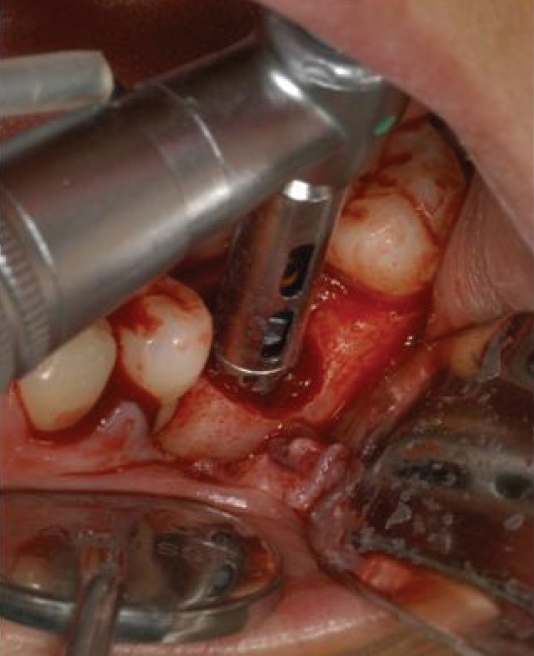

리무버를 적용할 때 주의할 사항은 역회전으로 고정을 하여야한다는 것이다. 이후에 라쳇이나 토크렌치등으로 잡고 흔들어서 제거해야만 제거가 용이하다. 그럼에도 불구하고 제거에 실패하는 경우에는 bur를 이용하여여 제거하는 수 밖에 없다(Fig. 7).

9. 치과임플란트 치아 주위염 치조골결손부 골이식술과 골유도재생술.

치주질환등으로 치과임플란트에 차107치조골결손부골이식술이나 차108조직유도재생술을 적용할 수 있다[8,9]. 이 두 술식은 굉장히 헷갈리는 술식이기도 하다. 둘다 골이식이 이루어지는 것이지만 차107 치조골결손부골이식술은 자가골이나 동종/이종골이 반드시 사용되어야한다. 반면에 차108조직유도재생술은 차폐막(membrane)의 사용이 반드시 필요하며 골이식은 시행될 수도 있고, 시행되지 않을 수도 있다. 이 둘 술식에 사용되는 동종/이종골은 반드시 보험등록이 가능한 재료이어야하며 술식이전에 건강보험심사평가원에 사전 등록되어 있어야 한다. 차폐막도 보험등재된 재료가 사전에 등록되어야 한다.

1) 골소실이 발생된 임플란트주위염 처치

모든 치주진료는 치석제거술이 먼저 시행되어야한다. 임플란트 8주위염도 마찮가지이다. 반드시 본원에서 시행될 필요는 없으며 최근에 타원에서 시행된 경우에는 내역설명이 필요하다. 이미 보철이 진행된 곳에 환형의 치조골소실이 발생된 경우에(Fig. 8) 치석제거와 함께 보철을 제거하고 cover screw 를 연결해주면 연조직이 치유된다(Fig. 9). 이후에 치조골결손부골이식술을 시행하고(Fig. 10) 일정기간 치유가 이루어진 후 다시 임플란트를 노출(치은박리소파술 적용)하여 치유지대주를 연결하고 재보철을 함으로서 임플란트를 재생하여 다시 사용해볼 수 있는 술식을 건강보험항목으로 진행할 수 있다.